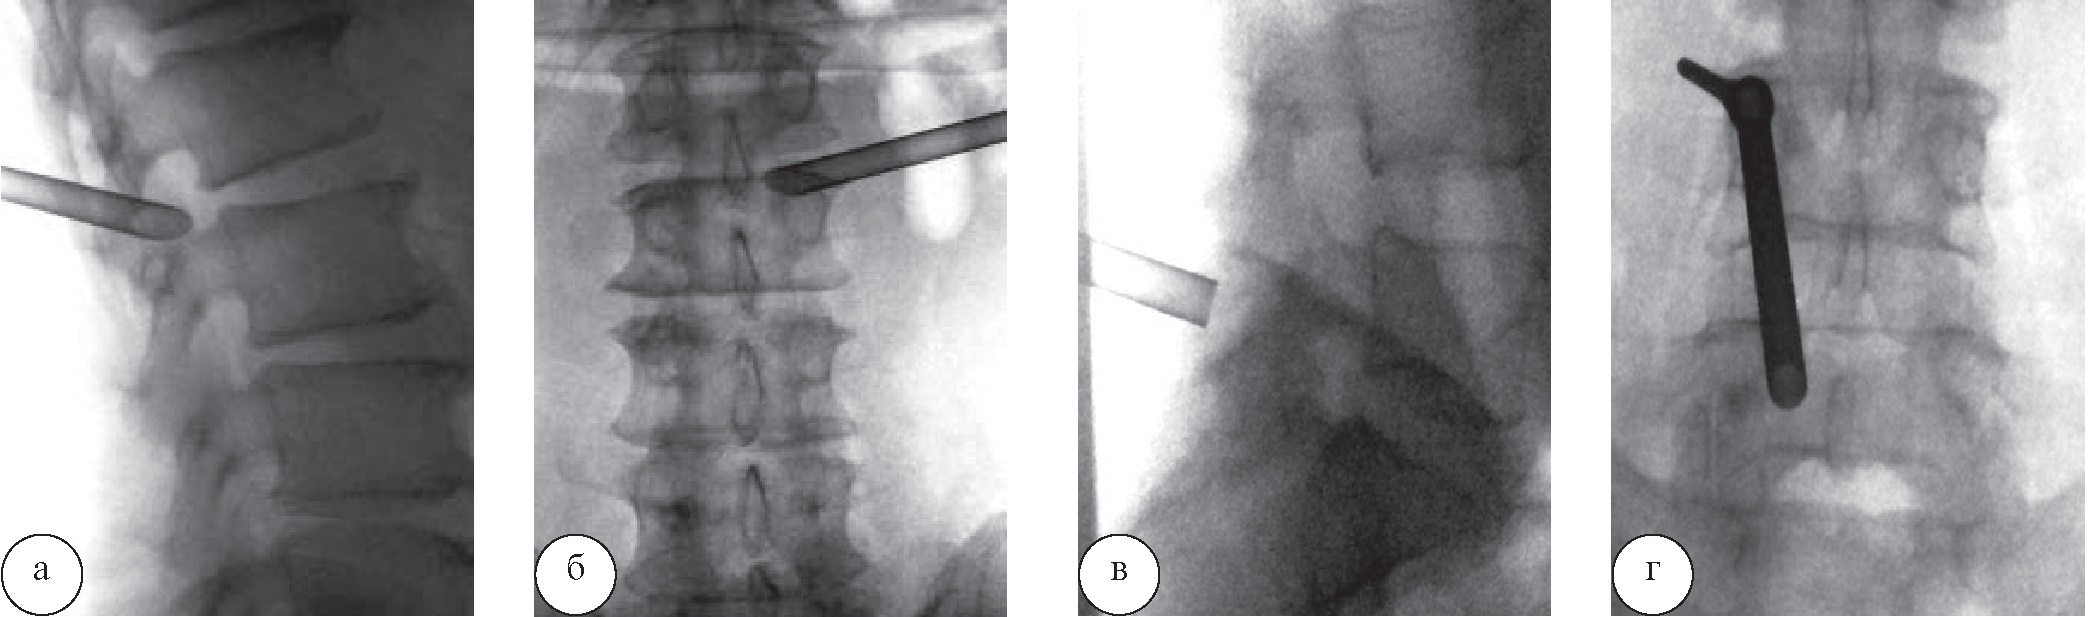

Перкутанные видеоэндоскопические вмешательства выполнены в 3 случаях со средней продолжительностью операции 80±10,8 мин (70–95 мин). Были использованы трансфораминальный, интерламинарный и трансламинарный чрескожные эндоскопические доступы (рис. 2).

Рис. 2. Интраоперационная спондилография: а, б – боковая и прямая проекции, отображающие положение рабочей канюли при правостороннем трансфораминальном эндоскопическом доступе на LIV–LV; в, г – те же проекции при трансламинарном (LV) доступе

Эндоскоп направляли точно к области локализации кисты через рабочую канюлю диаметром 7,5 мм. Современные видеоэндоскопические системы в жидкой среде 0,9% раствора хлорида натрия позволяли осматривать операционное поле в формате высокой четкости и без труда дифференцировать капсулу кисты на протяжении всей операции (рис. 3).